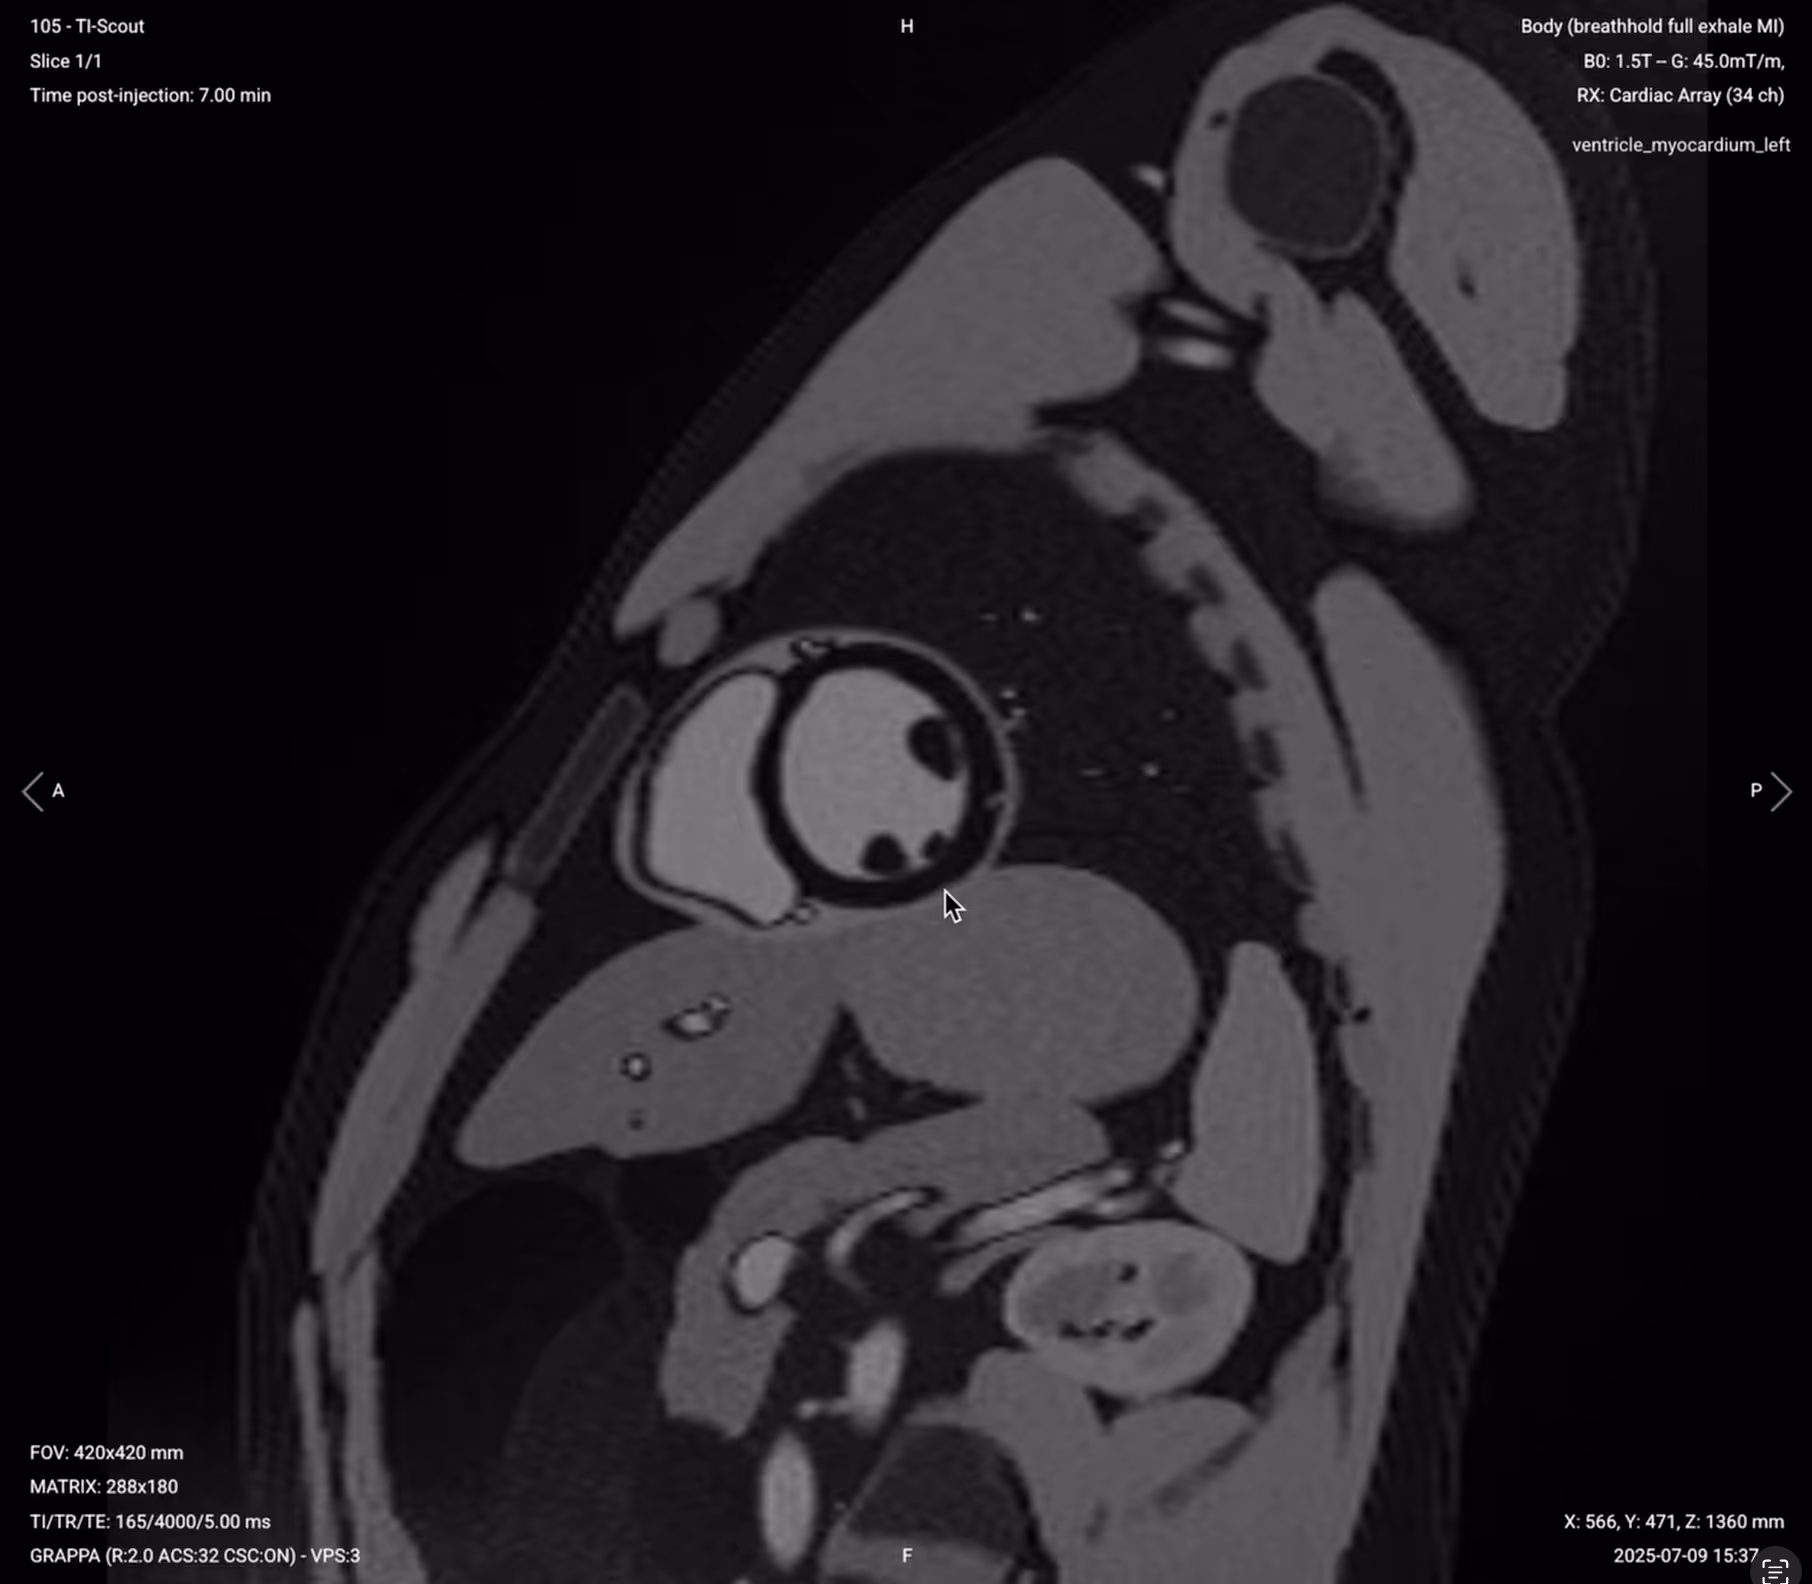

3. TI Scout – Finding the Myocardium Null Point

The TI Scout sequence shows multiple images with different inversion times. The goal is to find the exact timing that nulls healthy myocardium so it appears completely black.

The TI value from this image (typically 200–250 ms at 1.5T) will be used for all late enhancement sequences.

Run the TI Scout 8–10 minutes after contrast injection.

✅ Correct Planning:

Correct Planning – TI Scout

How to Read the TI Scout to Find the Right TI Value

Once your TI Scout has finished running, we must now read the resulting images to find the right TI value.

Scroll through its images and look at the areas where 1) the myocardium interfaces with the blood pool, and 2) the papillary muscles and epicardium cross over.

✅ TI Scout – Correct Image Example:

TI Scout – Correct Image Example

In these areas, look for these key features:

• Myocardium appears darkest

• Epicardium can be clearly seen as a bright line (but not too bright)

• Chest wall muscles also dark (confirming proper muscle nulling)

• Clear distinction between nulled myocardium and bright blood pool

The correct TI for late enhancement typically falls between 200–250 ms at 10–15 minutes post-contrast. Select the value that best nulls the myocardium.